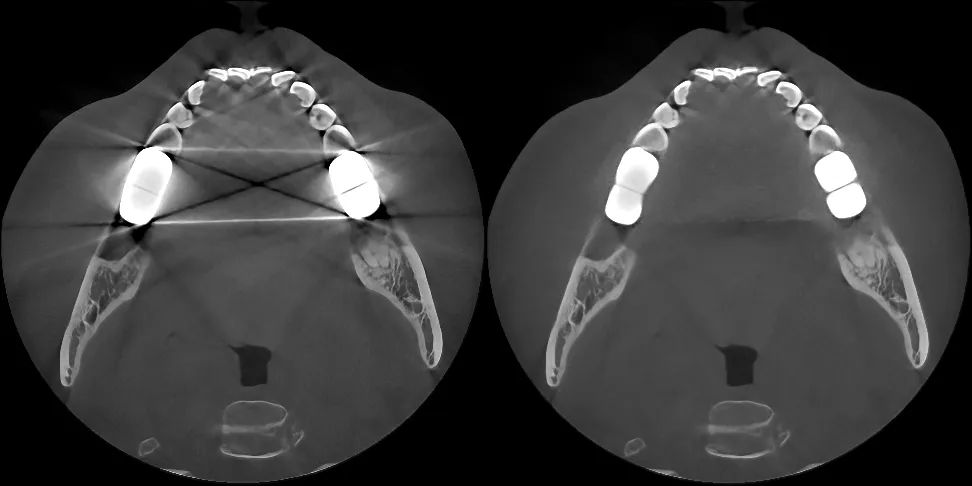

▶Currently, to address the challenge of complex pseudo-artifact interference, the all-new generation of "PD-MAR" technology has been developed to efficiently remove intraoral high-density material artifacts such as dental fillings, metal crowns, and implants. It also supports real-time comparison processing of pre-and post-images.

▲"PD-MAR" Advanced Artifact Removal Technology